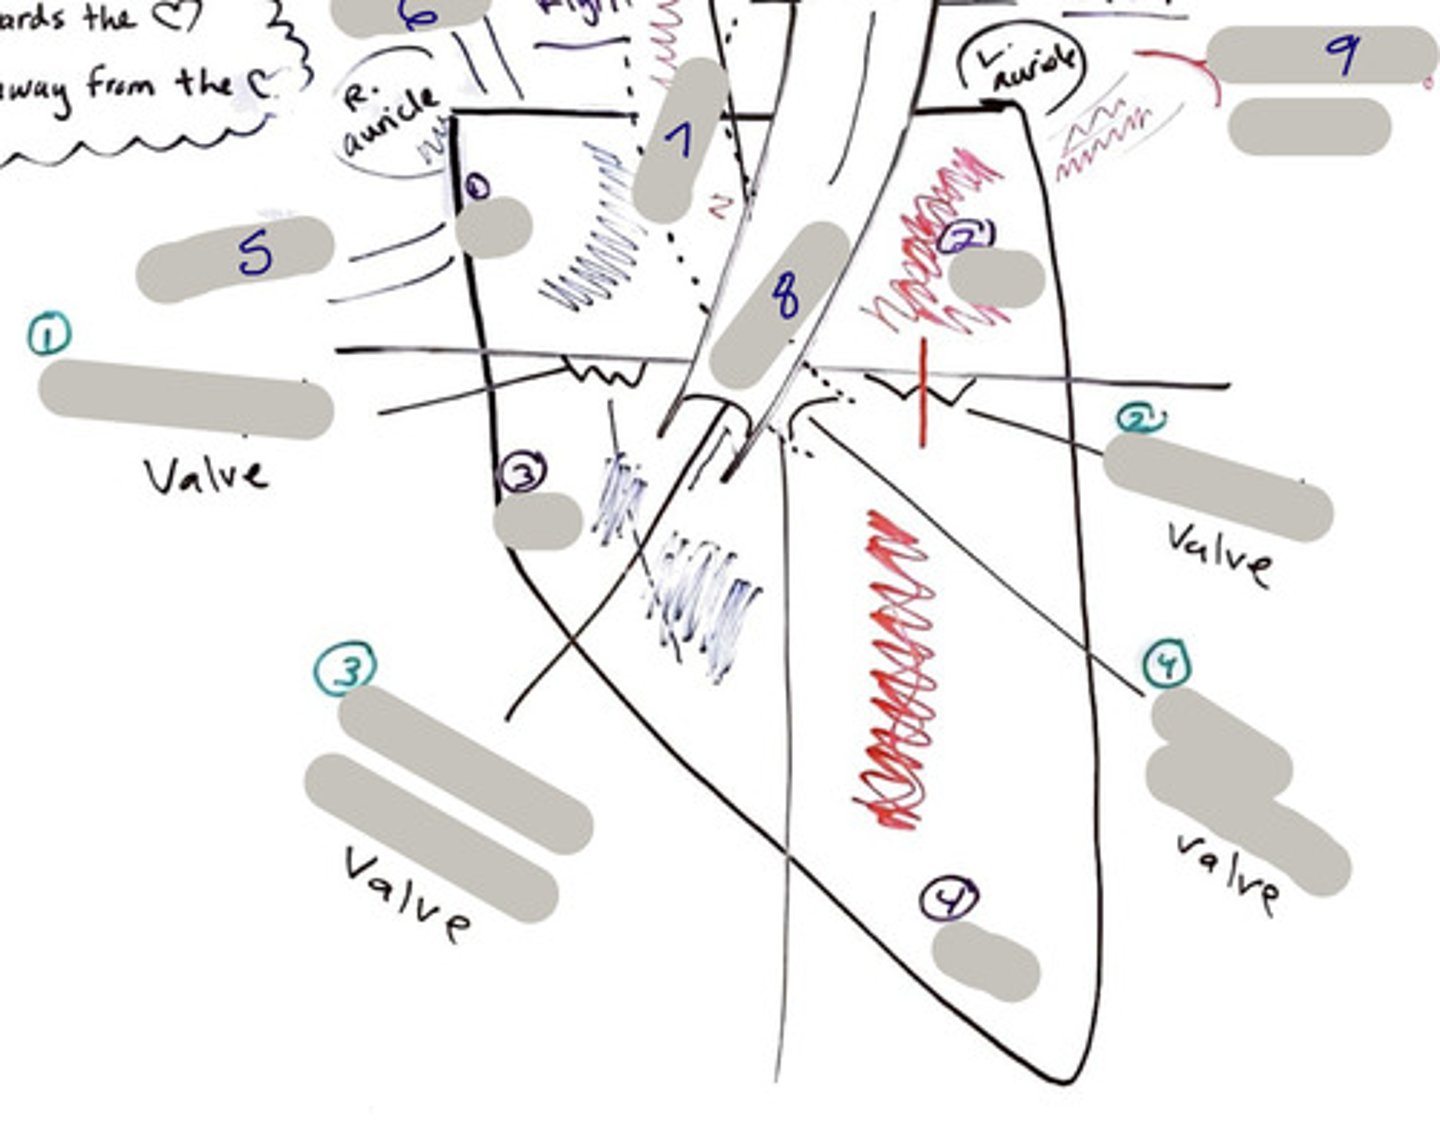

pulmonary trunk (model)

yellow sash of fat that tells you this if the front side of the heart (model)

t-shaped ribbon of fat on back side of heart (model)

Left ventricle (model)

has the most muscle mass because it has to pump blood to the whole body

apex (model)

base (model)

where everything connects